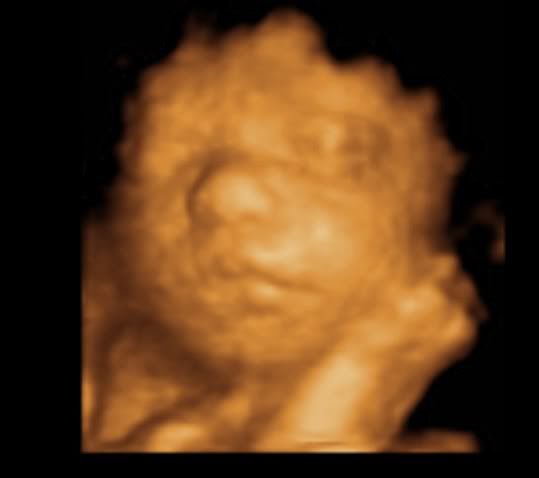

hegejenta30 Skrevet 19. mars 2011 #1608 Skrevet 19. mars 2011 Så herlige bilder av lille frøken krek! Skjønner godt du er forelsket!

Kokos Skrevet 19. mars 2011 #1611 Skrevet 19. mars 2011 Så fine bilder dere fikk! Der ser man jo vakre lille krek kjempegodt

^^Belle^^ Skrevet 19. mars 2011 Forfatter #1612 Skrevet 19. mars 2011 Så herlige bilder av lille frøken krek! Skjønner godt du er forelsket! Det gjør jeg også. Hun er jo det fiiiineste i hele verden. OOOOH, been there!!! Min var 56 cm lang da han ble født, så du kan jo tenke deg hvor deilig det var for ribsa på slutten.... Det kan jeg tenke meg. Håper ikke lille krek er så lang altså. Nusselige bilder! Takk. Så fine bilder dere fikk! Der ser man jo vakre lille krek kjempegodt Ja, noen av dem ble kjempefine. Nå gjenstår det bare å se om hun ligner på disse bildene når hun kommer ut.

Mazilla Skrevet 19. mars 2011 #1616 Skrevet 19. mars 2011 Jeg må ærlig innrømme at jeg synes alle 3D-ultralydbilder ser like ut.. Men ikke mindre koselig av den grunn, da! Kos deg i kveld! Selvfølgelig er det lov med sørlandschips på en lørdag!

^^Belle^^ Skrevet 19. mars 2011 Forfatter #1618 Skrevet 19. mars 2011 Jeg må ærlig innrømme at jeg synes alle 3D-ultralydbilder ser like ut.. Men ikke mindre koselig av den grunn, da! Kos deg i kveld! Selvfølgelig er det lov med sørlandschips på en lørdag! det har jeg også syntes frem til nå. Men vissheten om at det er vår jente vi ser...åh, jeg kan ikke la være å smile hver gang jeg ser bildene. Støttes! Og spretter i en pose med sørlandschips med spansk paprika! *mmmm* sørlandschips er bare best.

Småkjekset Skrevet 19. mars 2011 #1619 Skrevet 19. mars 2011 29 uker Så skjønn og fredfull hun ser ut Håper du får en fantastisk kveld med god snacks

Neala Skrevet 20. mars 2011 #1620 Skrevet 20. mars 2011 Åh, i alle dager, så fin hun ser ut! Tenker dere ikke gleder dere noe mindre nå